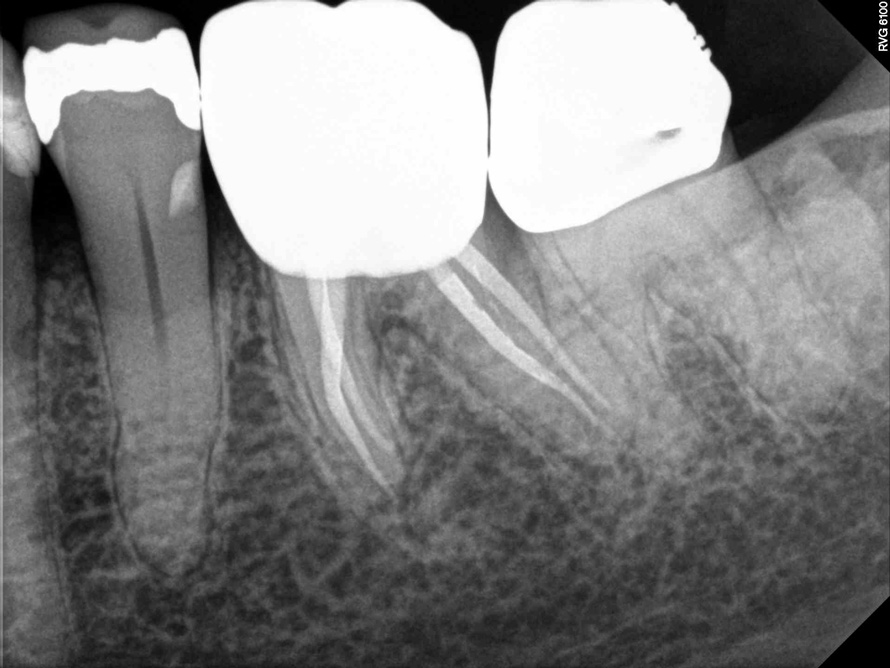

Fig 9. It is clinically acceptable to have results with the sealer puff (Figure 9) and without (Figure 10).

Figure 9

Fig 10. It is clinically acceptable to have results with the sealer puff (Figure 9) and without (Figure 10).

Figure 10